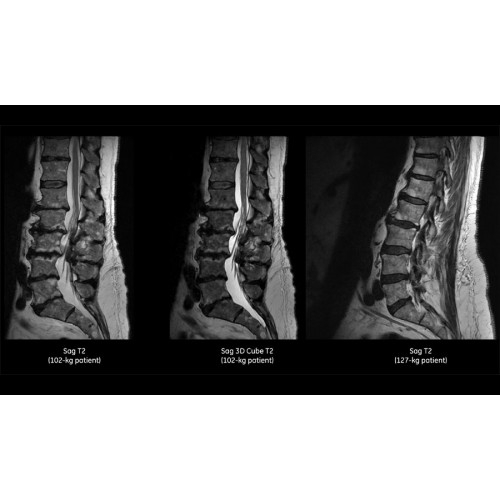

• Технология Digital Surround Technology (DST) — это новая технология объемной оцифровки данных, объединяющая сигналы от каждого элемента катушки. Прекрасное соотношение сигнал/шум и чувствительность поверхностных катушек в сочетании с превосходной однородностью и высокой проникающей способностью встроенной радиочастотной катушки — все это позволяет создавать качественные изображения не только позвоночника, но и всего тела.